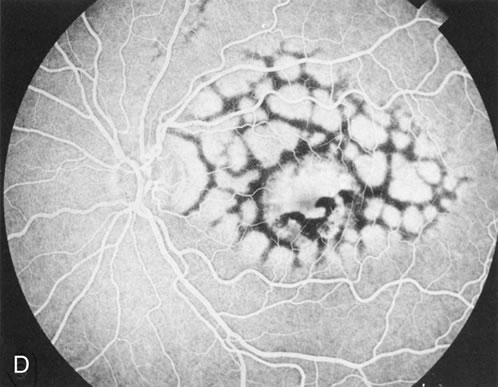

Of more clinical importance is the role of FA in the diagnosis and treatment of cystoid macular edema (CME) (Fig. 1C and D). Stereoscopic FA indicates that the leakage, which may be diffuse or have the typical petaloid stellate appearance of CME, can come from the perifoveal retinal capillaries, from the choroid through the RPE, or from a combination of both sources.4 With the recent suggestion that CME in RP may be successfully treated with acetazolamide,5, 6 FA is thus important to document the diagnosis of CME, establish the origin(s) of leakage, and follow patients during and after therapy.